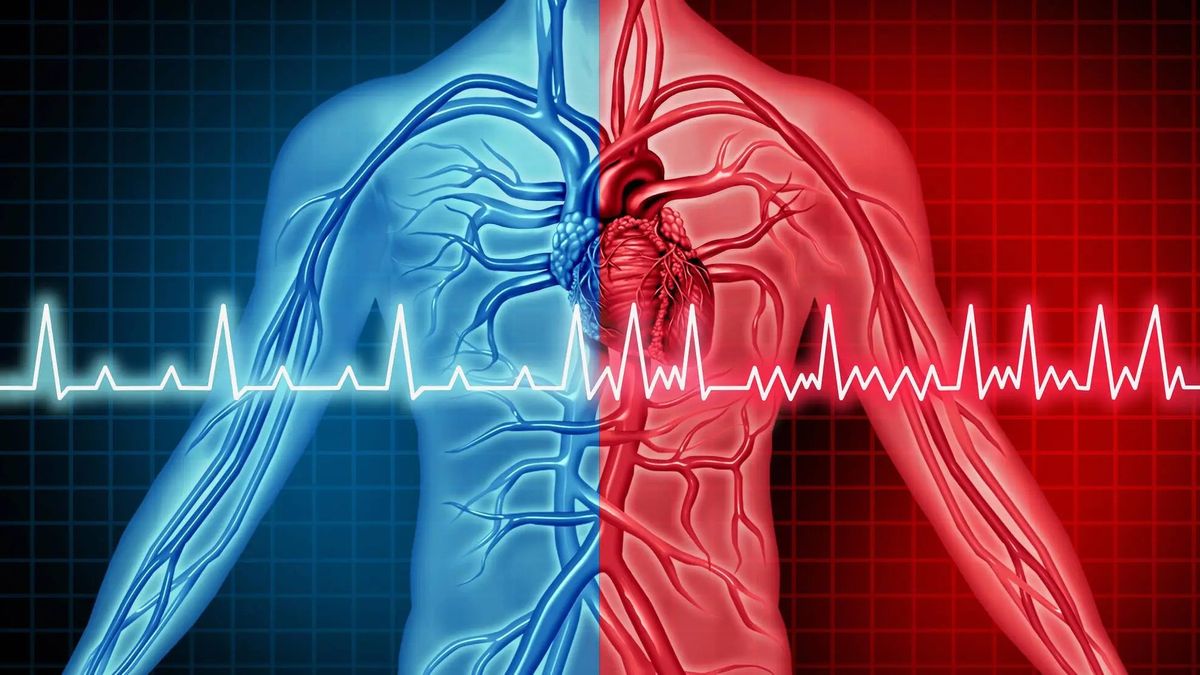

Így még sosem láthattad: életmentő projektre mondott igent Hide the Pain Harold – Videó

Ezért állt állt össze a Mentőalapítvány és a mémlegenda.

Tatabányai hős lány: 17 éves diák mentette meg az idős férfit

Hazafelé menet, gyorsan megállt életet menteni.